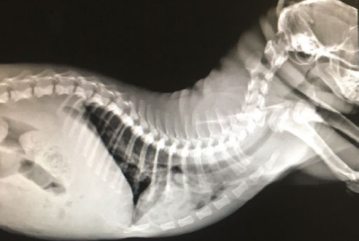

При проведении рентгенографии, у кошек с врожденной формой гипотиреоза, отмечается укорочение костей и их деформация, также отмечают признаки констипации, реже мегаколон (рис. 2).

Рис. 2. Деформация скелета у кошки с врожденным гипотиреозом